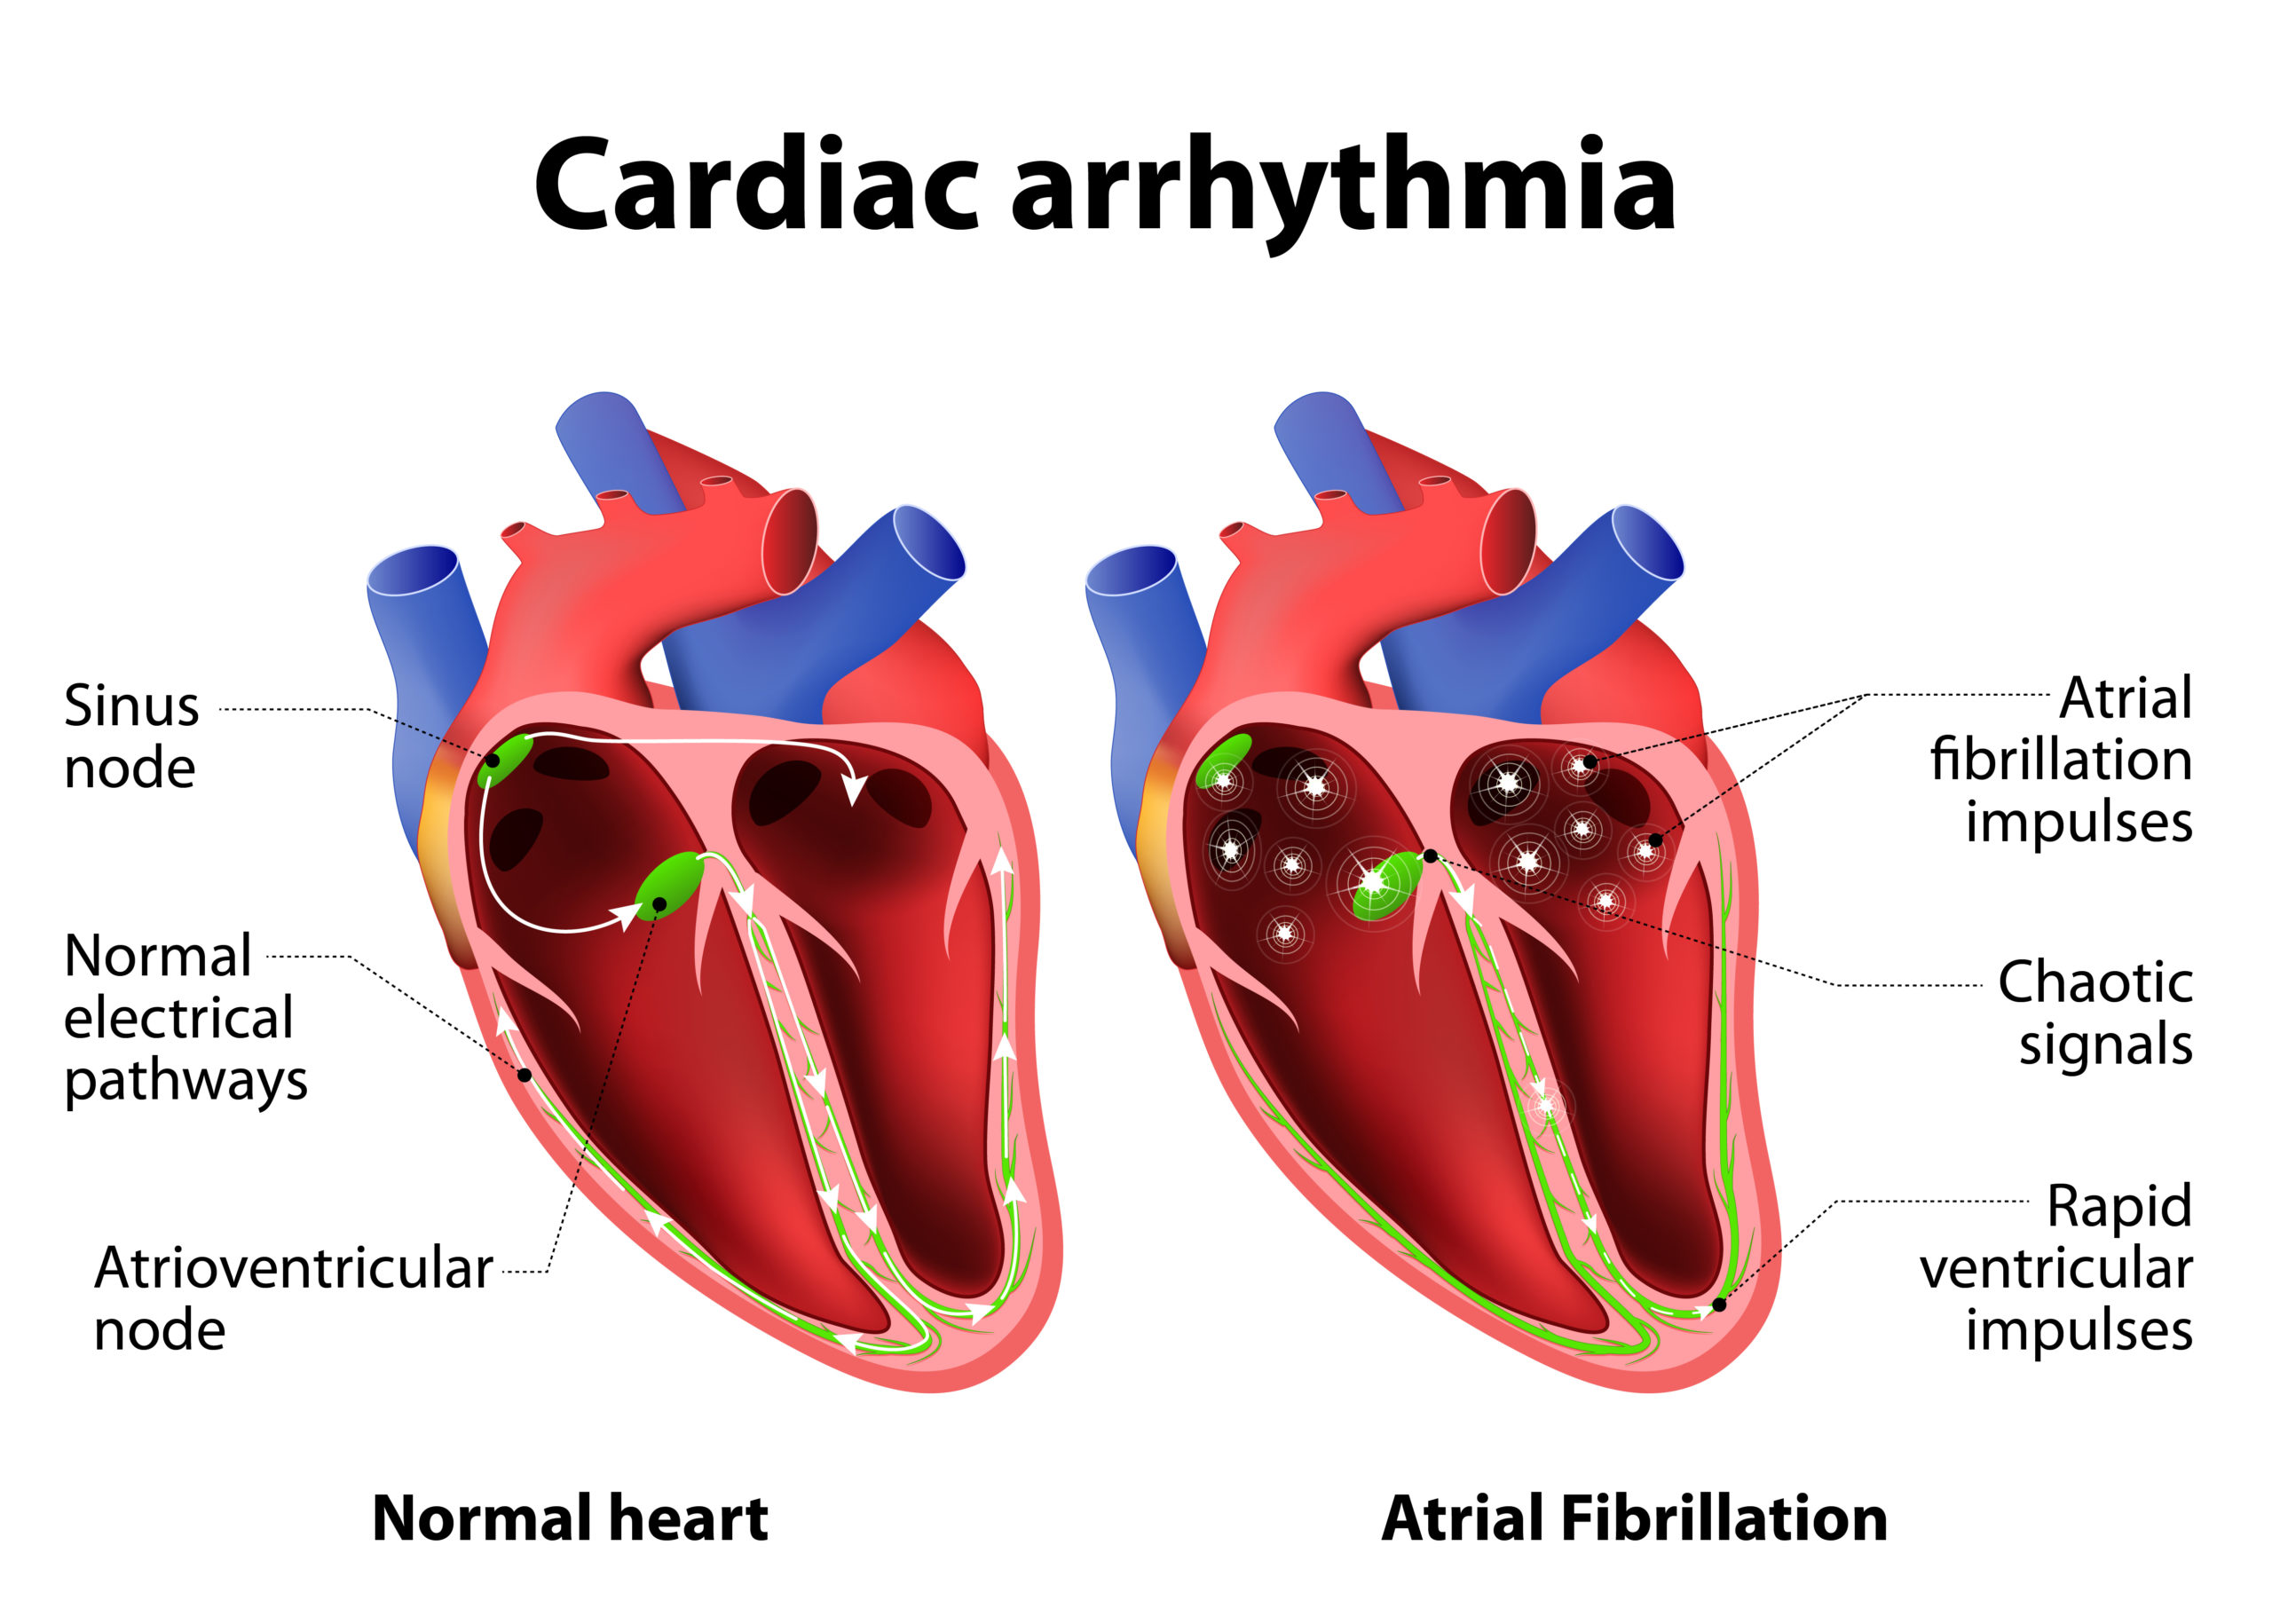

The primary goal of catheter ablation (CA) in patients with atrial fibrillation (AF) is to reduce symptom burden and ...